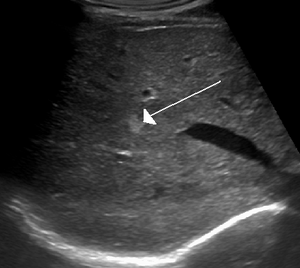

On ultrasound, cavernous haemangiomas in liver appeared as homogenous, hyperechoic lesions with posterior acoustic enhancement. On CT or MRI scans, it shows peripheral globular/nodular enhancement in the arterial phase, with portions of attenuation of enhancing areas. In the portal venous phase, it shows progressive centripetal enhancement. In delayed phase, it shows retention of contrast. It shows a high signal on T2 weighted images.[24]